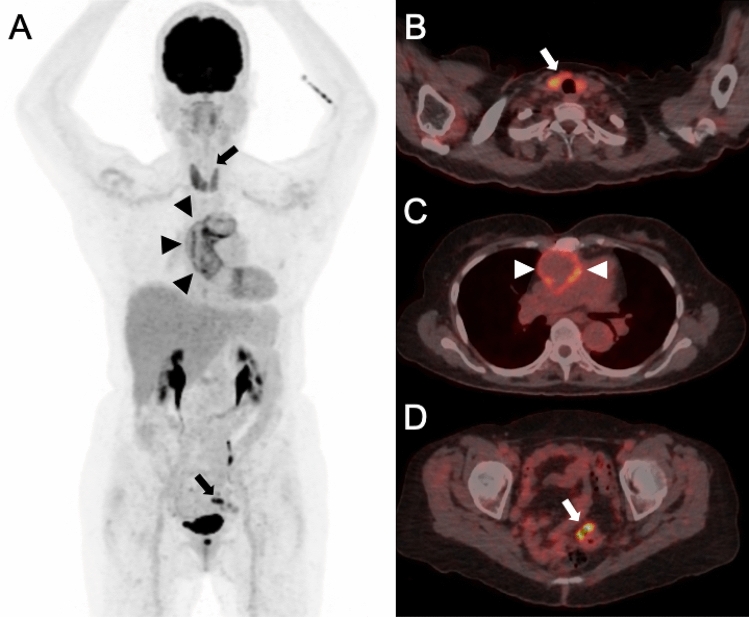

Figure 1.

A 70-year old female patient was referred to PET/CT 14 months after the initial diagnosis of a vascular graft infection due to Streptococcus hominis. The reason for referral was whether antibiotic treatment could be stopped. PET/CT [maximum intensity reconstructions of PET (A) and fused PET/CT images (B–D)] showed diffuse FDG uptake along the ascendens graft (Index surgery: aortic arch replacement with 28 mm Intergard® prosthesis) (black arrow heads in A, white arrow heads in C) which was focally pronounced (A) indicating persistent infection. Antibiotic treatment was continued for another eight months and then successfully stopped (no signs for recurrence at the last control seven months later). The patient had known thyroiditis, which presented with diffuse FDG uptake (upper black arrow in A, white arrow in B); this finding was not evaluated for impact on patient management in our study, as it was already known prior to PET/CT. An unknown and relevant incidental finding was detected in the sigmoid colon with intense focal FDG uptake (lower black arrow in A, white arrow in D). This PET/CT finding was rated to have impact on patient management—subsequent coloscopy and resection revealed a colonic polyp with dysplasia.